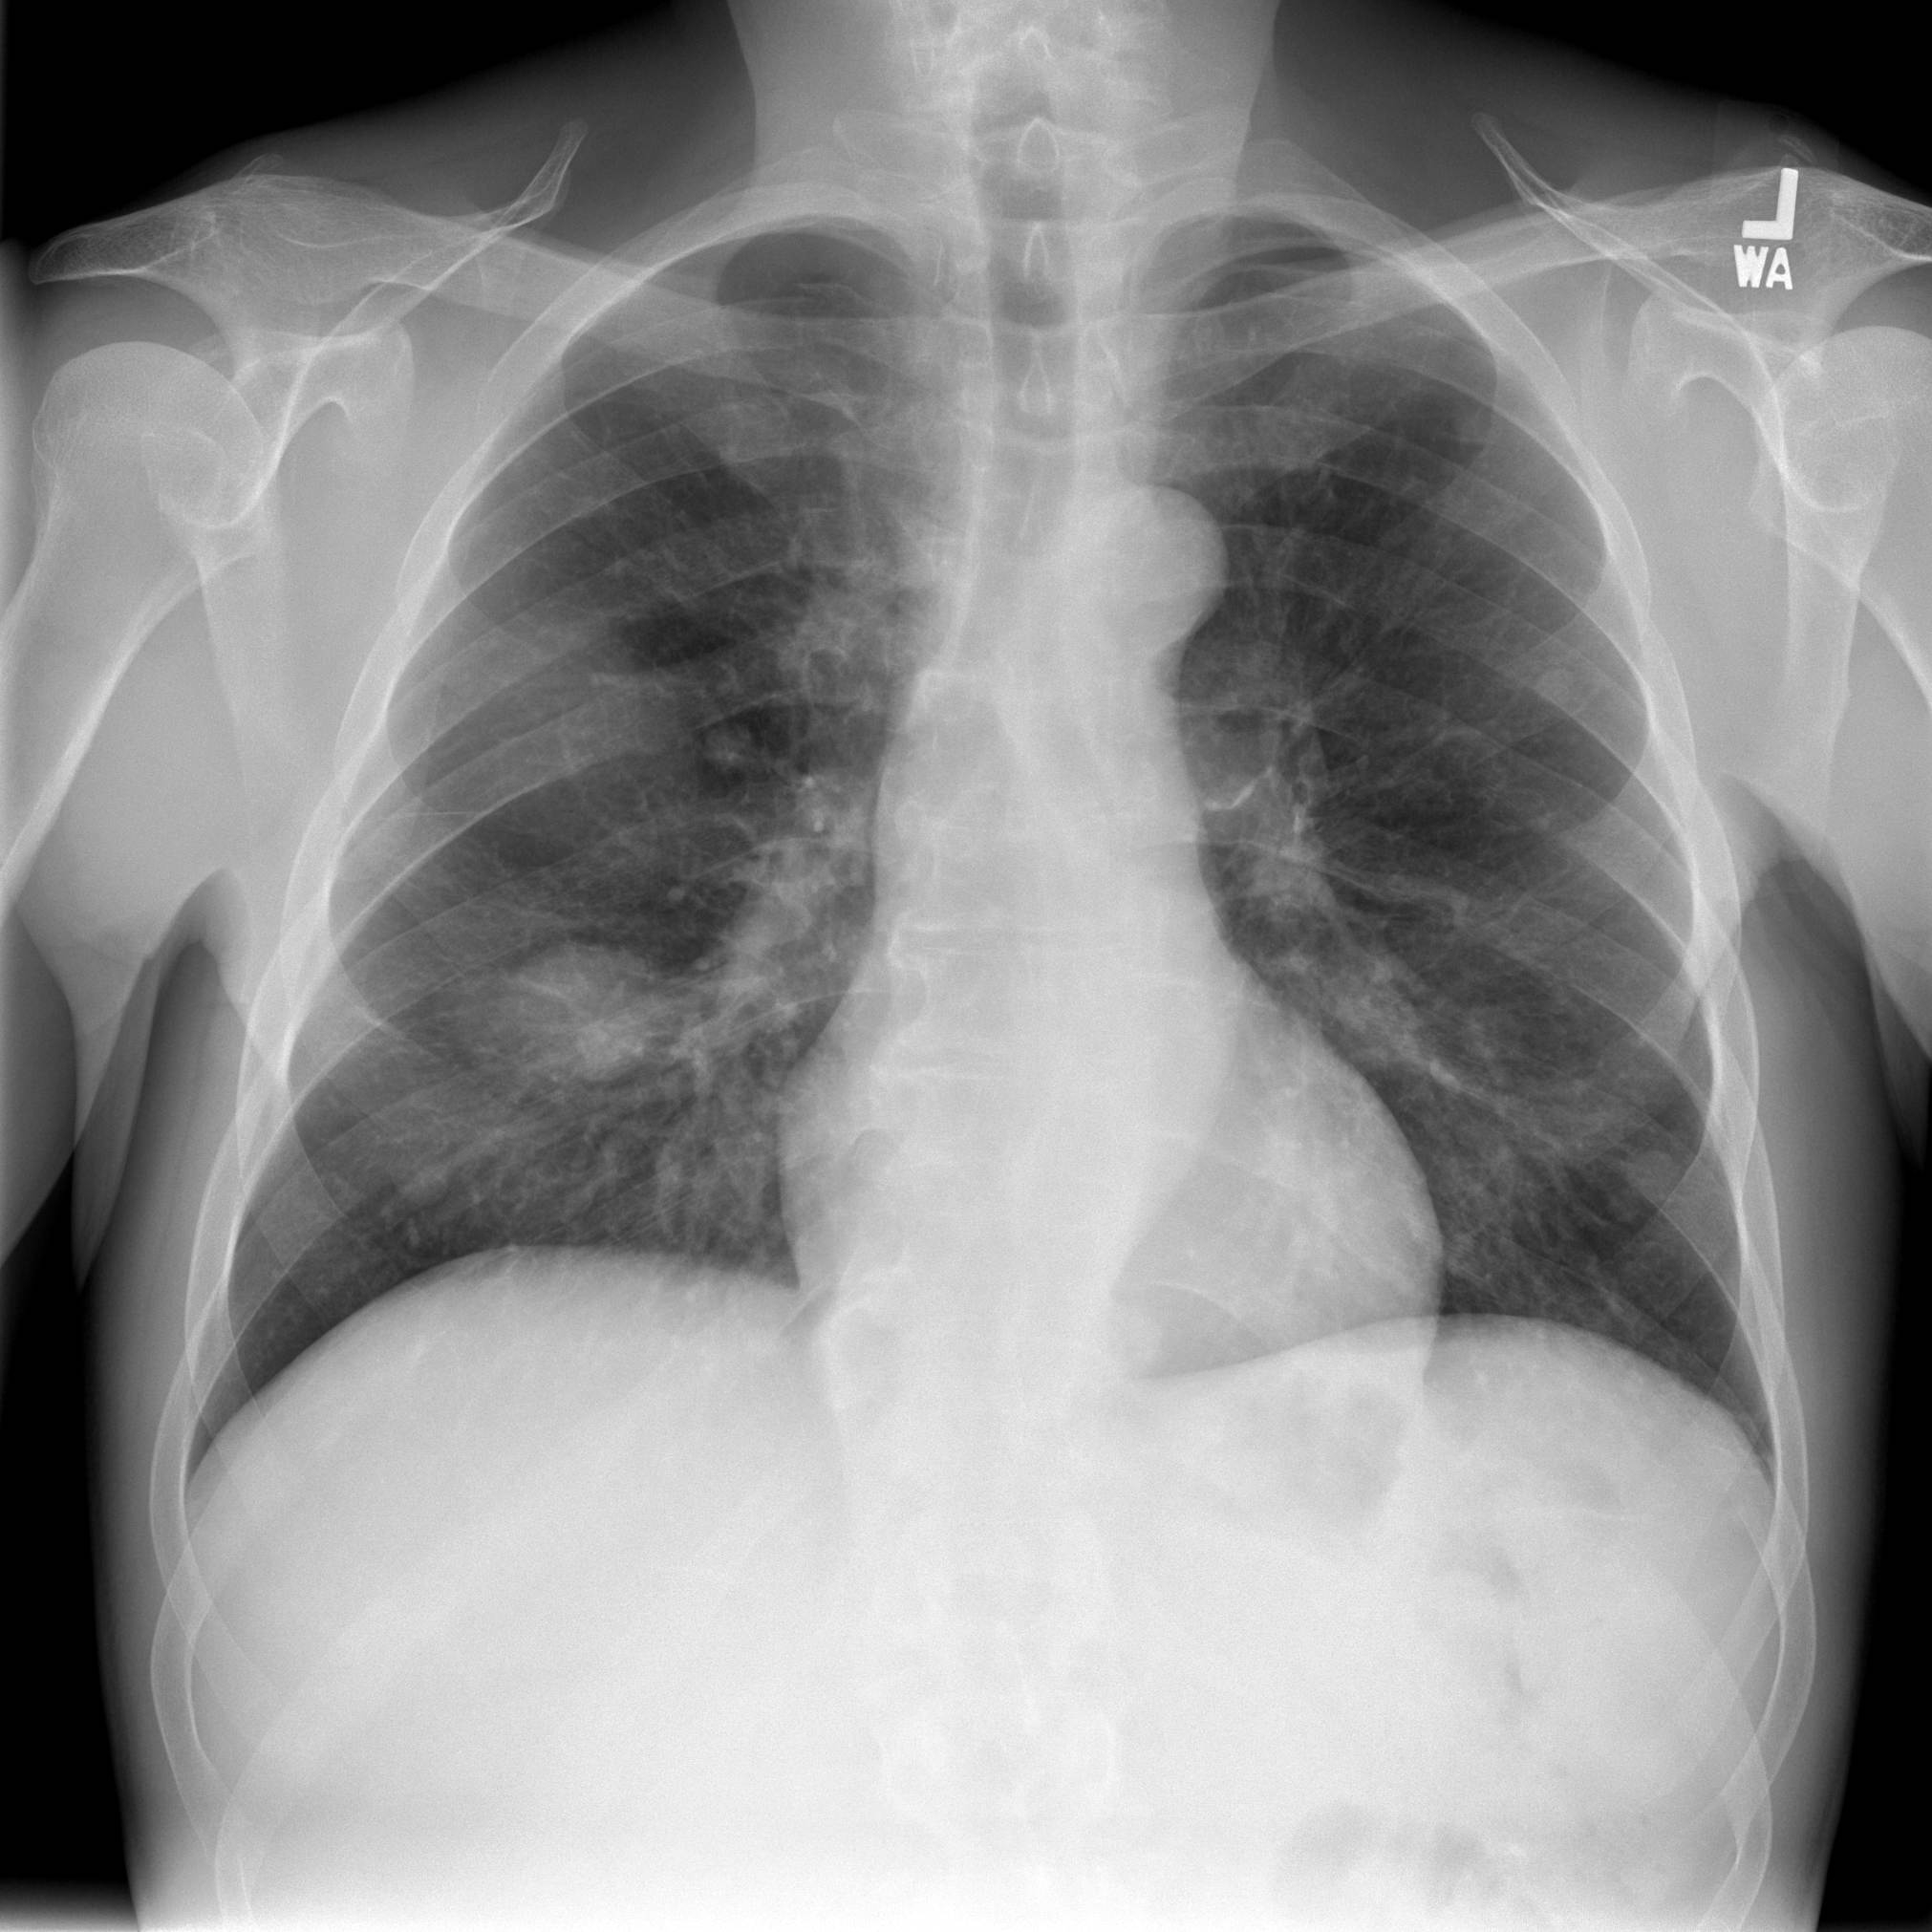

IMPRESSION:

1. Right lung mass with multiple bilateral pulmonary nodules. 32 mm x 17

mm sclerotic lesion within the right iliac bone. This likely represents a

primary lung cancer with metastatic lesion to the pelvis.